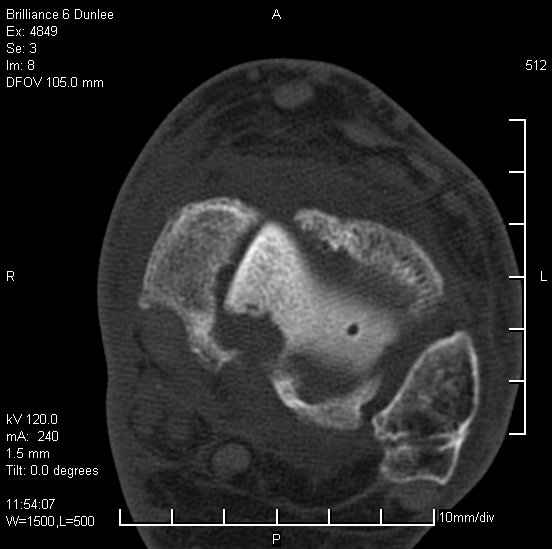

На лечении находится пациент 35 лет. Травма в сентябре 2008 г.- открытый вывих таранной кости

В день травмы ПХО, вправление вывиха, трансартикулярная фиксация. Рана зажила первично. С января нагрузка на конечность. С конца апреля- болевой синдром. На рентгенограммах и КТ признаки ас. некроза таранной кости, артроз подтаранного и голеностопного суставов.

У больного тотальный ас. некрох блока таранной кости, заинтересованы голеностопный и подтараный суставы. Эндопротезирование маловероятно на некротизированную кость. Изолированный подтаранный артродез таран не спасет.При артродезе всю некротизированную кость придется убрать.А далее замещение либо за счет большеберцовой кости, или удлинение на регенерате.